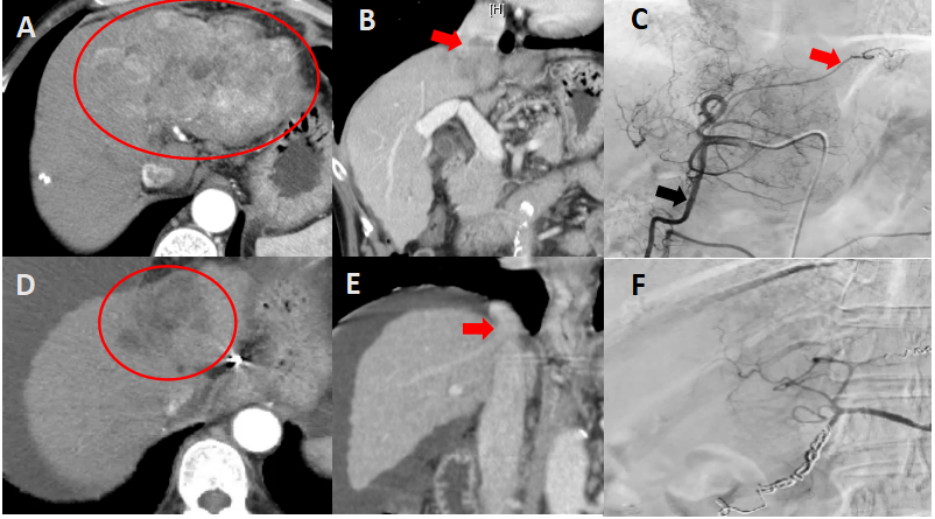

图A-C 术前上腹部增强CT提示肝左叶巨大占位,增强示明显强化(图A,红色圈);伴肝静脉、下腔静脉及门静脉左支侵犯(图B,红色箭头);DSA造影示肝内团块状肿瘤染色,应用弹簧圈封闭胃十二指肠动脉(图C,黑色箭头)及胃右动脉分支(图C,红色箭头)。

图D-F,4次HAIC治疗后上腹部增强CT提示肝内肿瘤明显缩小,无强化(图D,红色圈),肝静脉、下腔静脉及门静脉癌栓消失(图E,红色箭头);DSA造影示肿瘤染色消失(图F)。